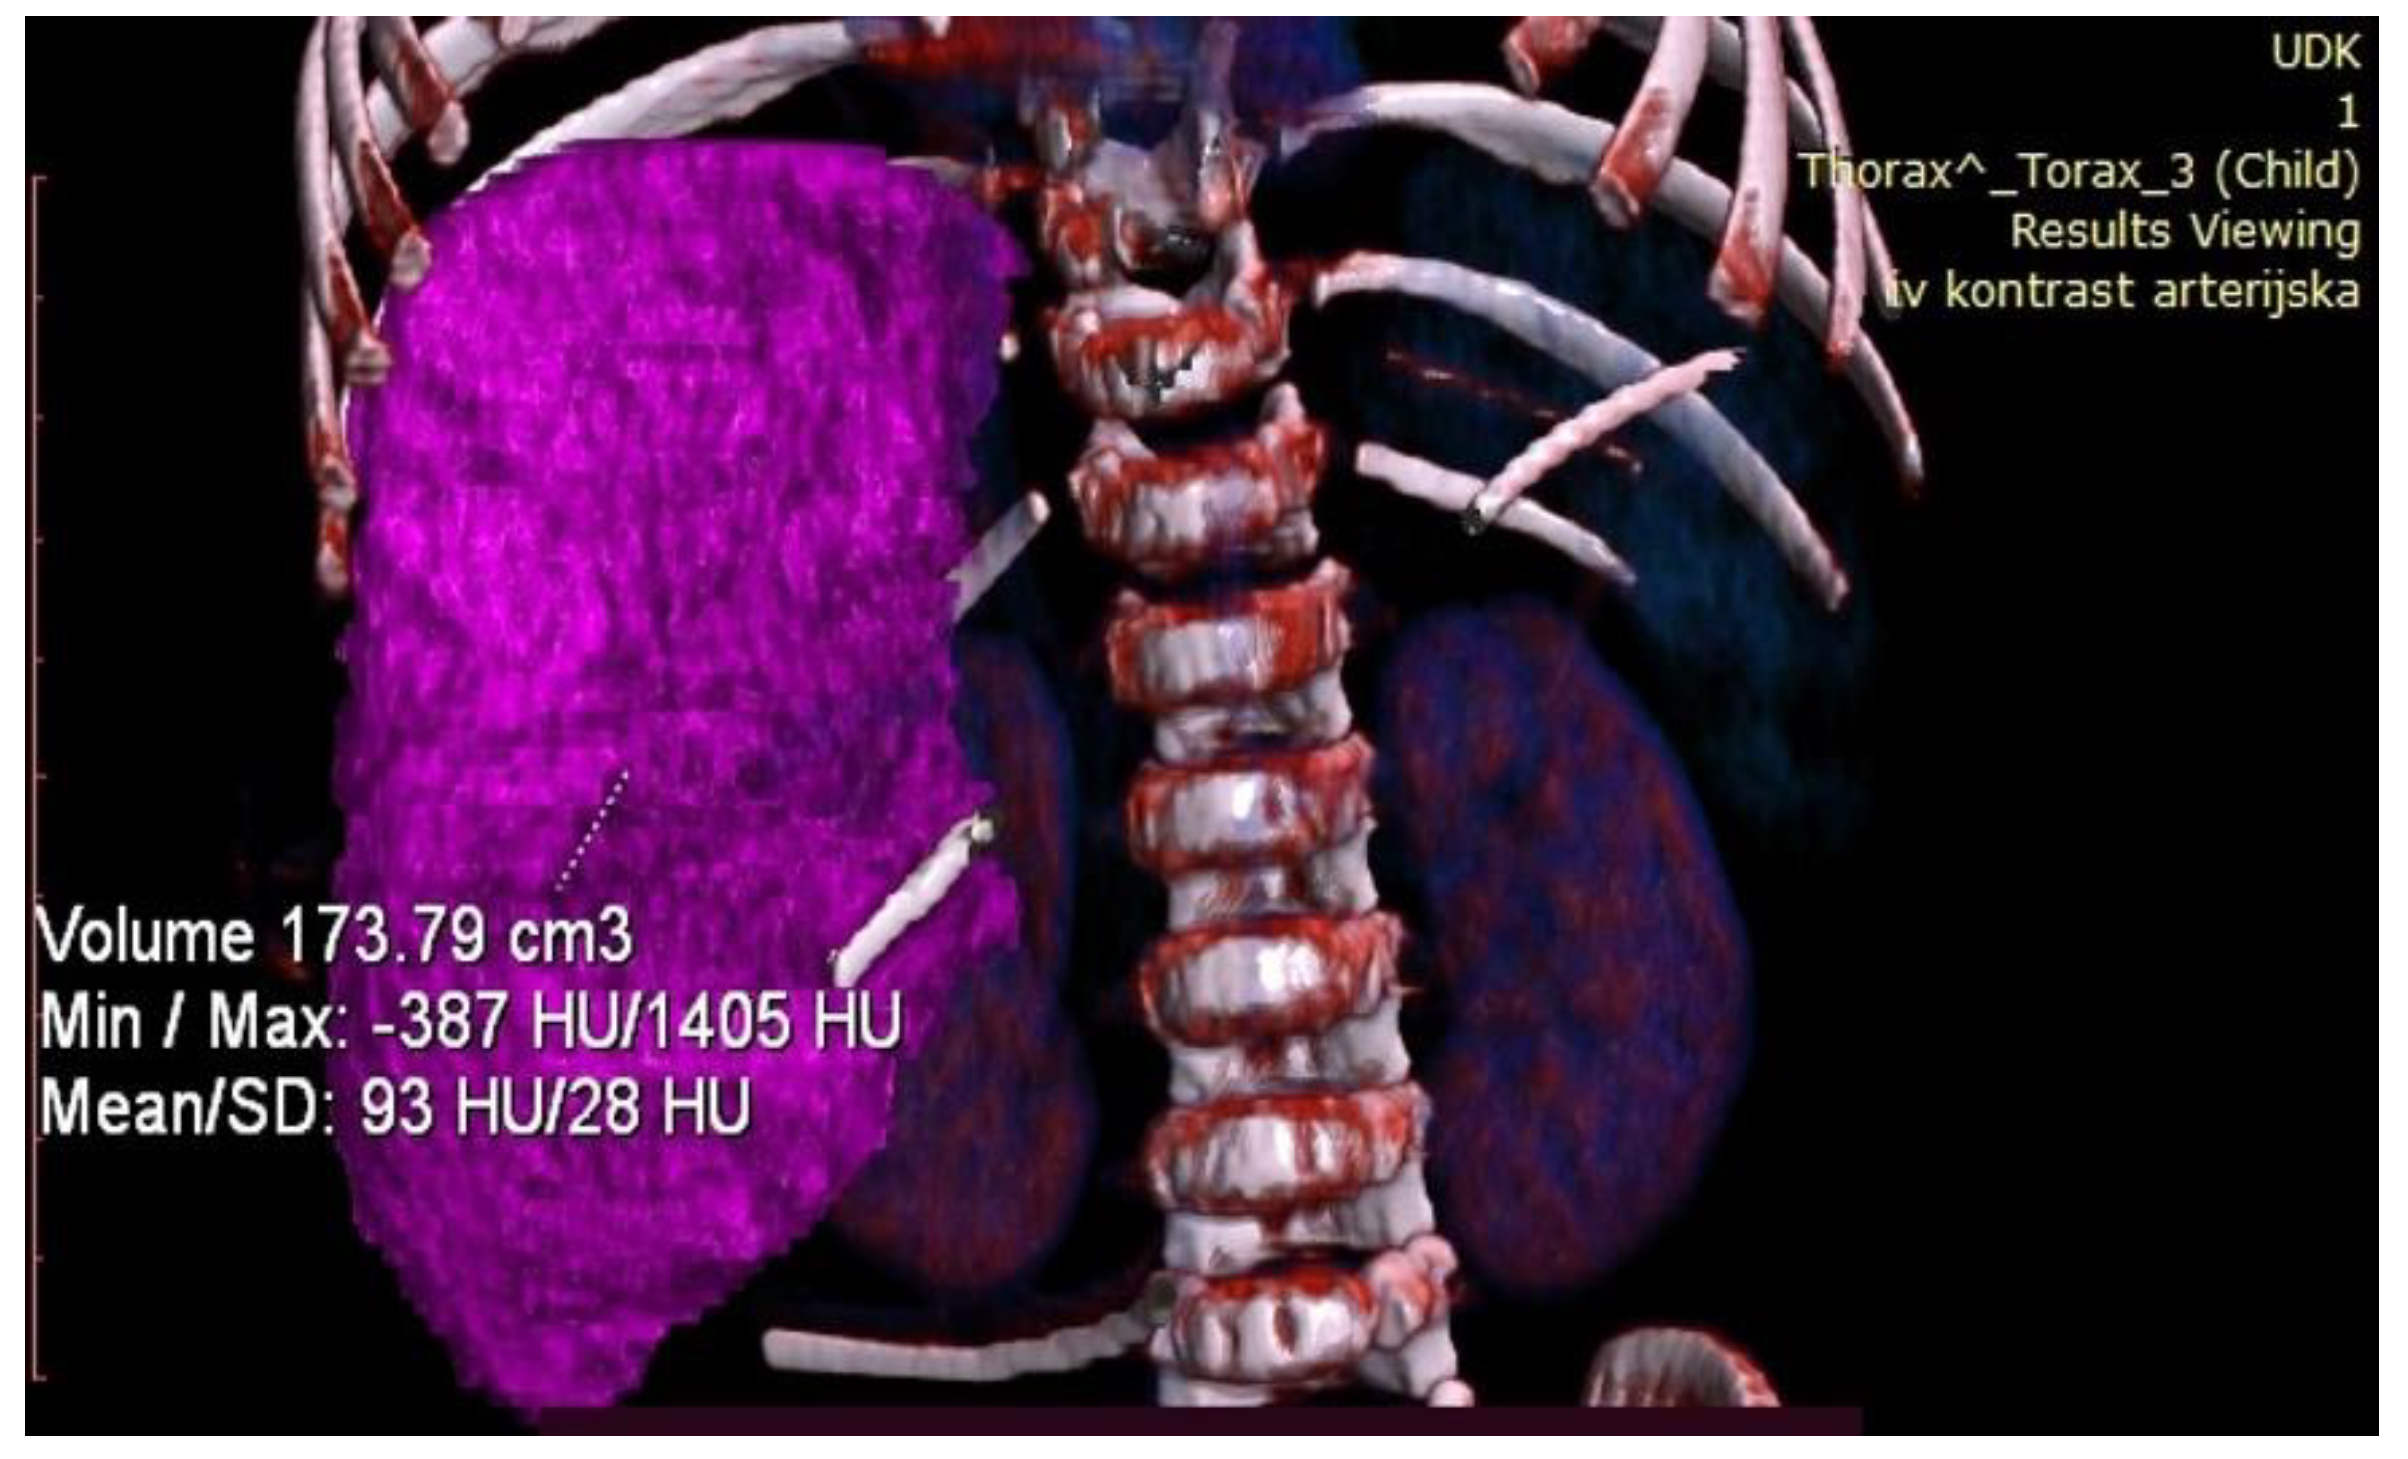

Control volumetry performed on the seventh postoperative day showed that the FLR was 173.79 cm3, which represented a 74.1% gain in volume, and a FLR/ETLV ratio of 43% (Figure 7).

Figure 7.

Postoperative volumetry of the liver showing future liver remnant.